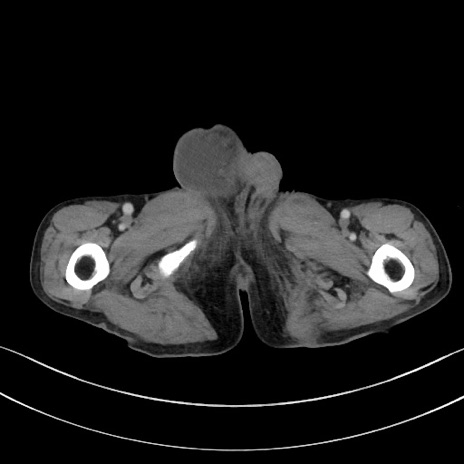

症例3(横断像)

【症例】 70歳代男性

【主訴】右鼠径部腫瘤、疼痛

【現病歴】本日朝より上記主訴あり、受診。

【既往歴】膀胱癌にて膀胱全摘、両側尿管皮膚瘻

【データ】WBC 5600、CRP 0.56